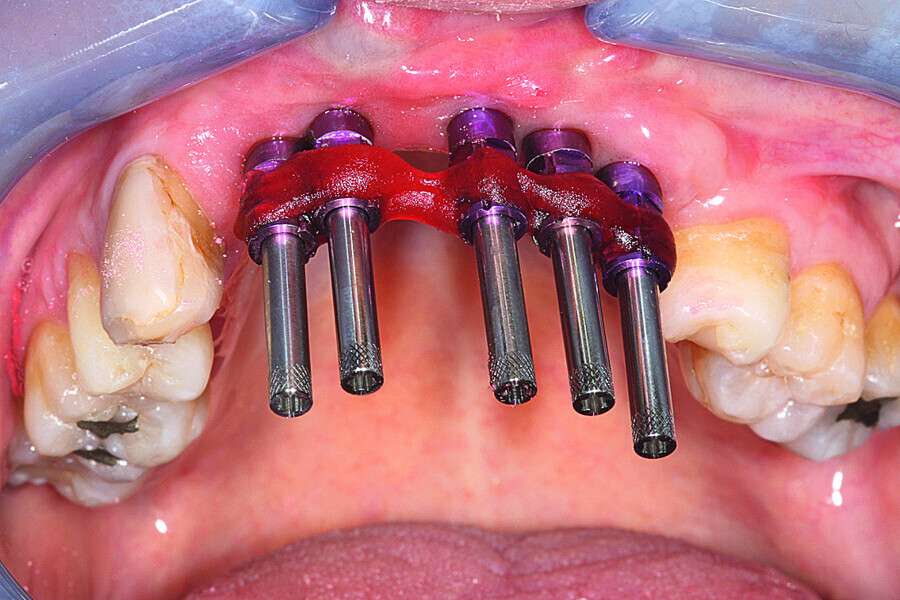

Fig. 17: Loaded implants, healing abutments in situ.

Fig. 18: The healing abutments were removed and replaced with pick-up impression copings secured with self-curing resin.

Fig. 19: Removal of the impression and fitting of the impression copings with their laboratory equivalent.